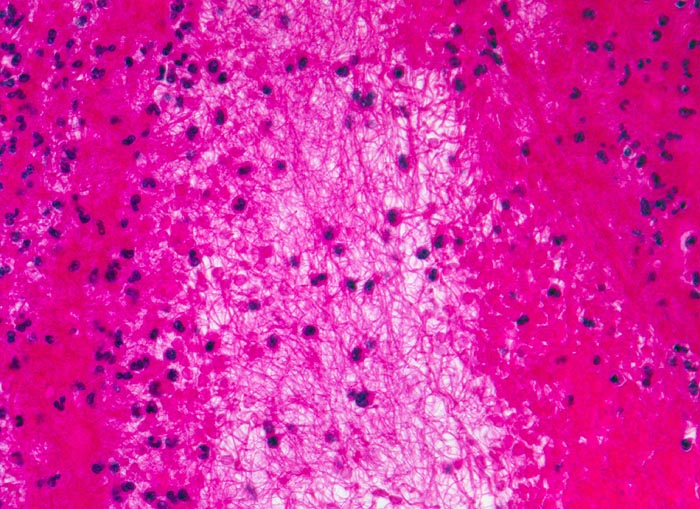

Korallenstockthrombus (Abscheidungsthrombus)

Abscheidungsthrombus bestehend aus abwechselnden Schichten von zerfallenen Thrombozyten mit Fibrin und fädigem Fibrin, in dem sich neutrophile Granulozyten und Erythrozyten verfangen haben.

Makroskopisch sind die verschiedenen Schichten als sogenannte Zahn'sche Linien identifizierbar: hellere Schichten von Fibrin mit Thrombozyten und dunklere Schichten mit Fibrin, Erythrozyten und Granulozyten.

Histologie

320